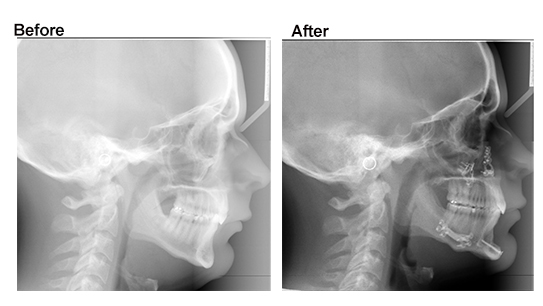

- Cephalometric X-rays

3. Custom Jaw Surgery vs Traditional Jaw Surgery

- Normal Jaw Surgery: Traditional surgical planning using physical models and 2D imaging. Effective, covered by insurance if medically necessary.

- X-rays (ceph + panoramic)